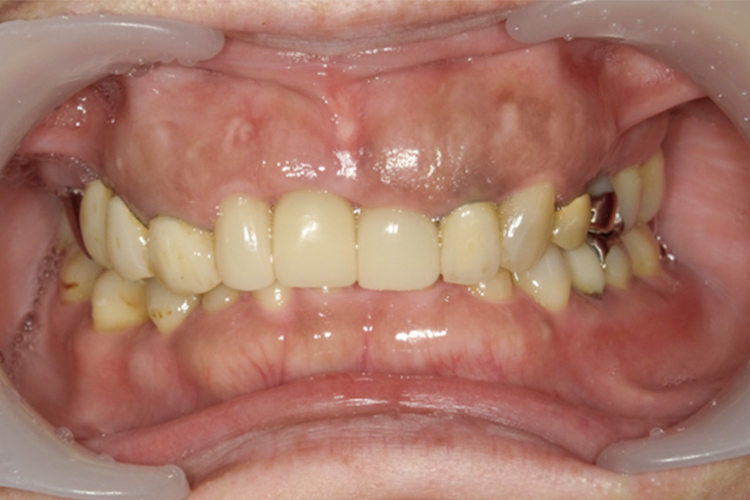

治療前

治療後